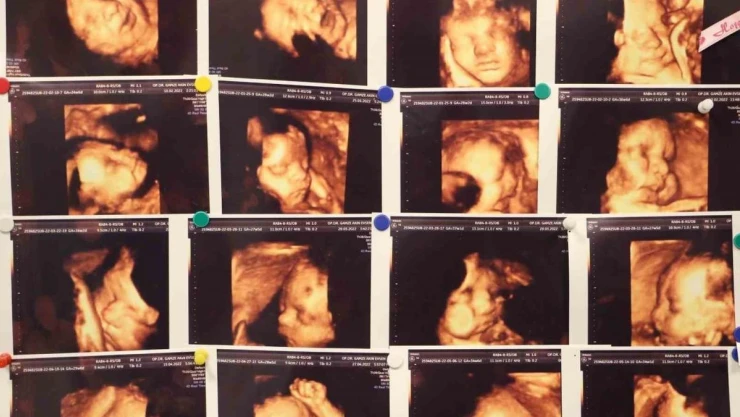

Memorial Hastanesi Kadın Hastalıkları ve Doğum Uzmanı Op. Dr. Gamze Akın Evsen, çocuk sahibi olmaya hazırlanan çiftlerin yaşadığı en büyük travmalardan biri olan gebelik kayıpları, çoğu anne adayının psikolojisinin bozulmasına ve çaresizlik hissine kapılmasına neden olduğunu belirterek, Klinik olarak saptanan gebeliklerin yüzde 10-15'i düşükle sonuçlanmakla beraber bu durumun tekrar etmesi yani tekrarlayan gebelik kayıplarında oran Yüzde 3 ila 5'tir dedi.

Memorial Hastanesi Kadın Hastalıkları ve Doğum Uzmanı Op. Dr. Gamze Akın Evsen, çocuk sahibi olmaya hazırlanan çiftlerin yaşadığı en büyük travmalardan biri olan gebelik kayıpları, çoğu anne adayının psikolojisinin bozulmasına ve çaresizlik hissine kapılmasına neden olduğunu belirterek, "Klinik olarak saptanan gebeliklerin yüzde 10-15’i düşükle sonuçlanmakla beraber bu durumun tekrar etmesi yani tekrarlayan gebelik kayıplarında oran Yüzde 3 ila 5’tir" dedi.

Kadın Hastalıkları ve Doğum Uzmanı Op. Dr. Gamze Akın Evsen, gebelik kayıplarında en sık kromozomal sıkıntılar olmakla beraber, genetik anomaliler, hormonsal sıkıntılar, kan pıhtılaşması, rahmin yapısal bozuklukların olduğunu ve tekrarlayan gebelik kayıplarının ise öncelikle anne ve babanın kronik hastalıkları, tıbbi öyküleri, ailede mevcut genetik hastalıkları gibi durumların ayrıntılı bir şekilde sorgulanmasıyla ortaya çıkacağını söyledi.